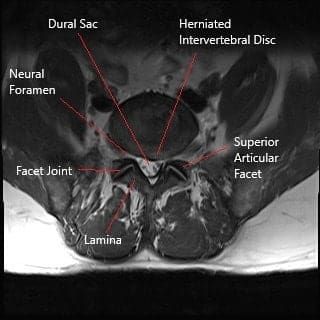

A lumbar disc herniation occurs when the nucleus pulposus (the soft, gelatinous center of the intervertebral disc) protrudes through a tear in the annulus fibrosus (the tough outer layer of the disc). The herniated disc may compress spinal nerves or the dural sac, leading to symptoms such as pain, numbness, tingling, and weakness in the lower back, legs, or feet. Factors that contribute to disc herniation include:

The lumbar spine consists of five vertebrae (L1-L5) and the intervertebral discs between them. These discs act as shock absorbers, allowing for movement and flexibility. The spinal cord runs through the spinal canal, and nerves branch off from the cord through openings between the vertebrae, known as foramina. These nerves control sensations and movements in the lower back, legs, and feet. A herniated disc can compress these nerves, leading to symptoms like pain, numbness, and muscle weakness.